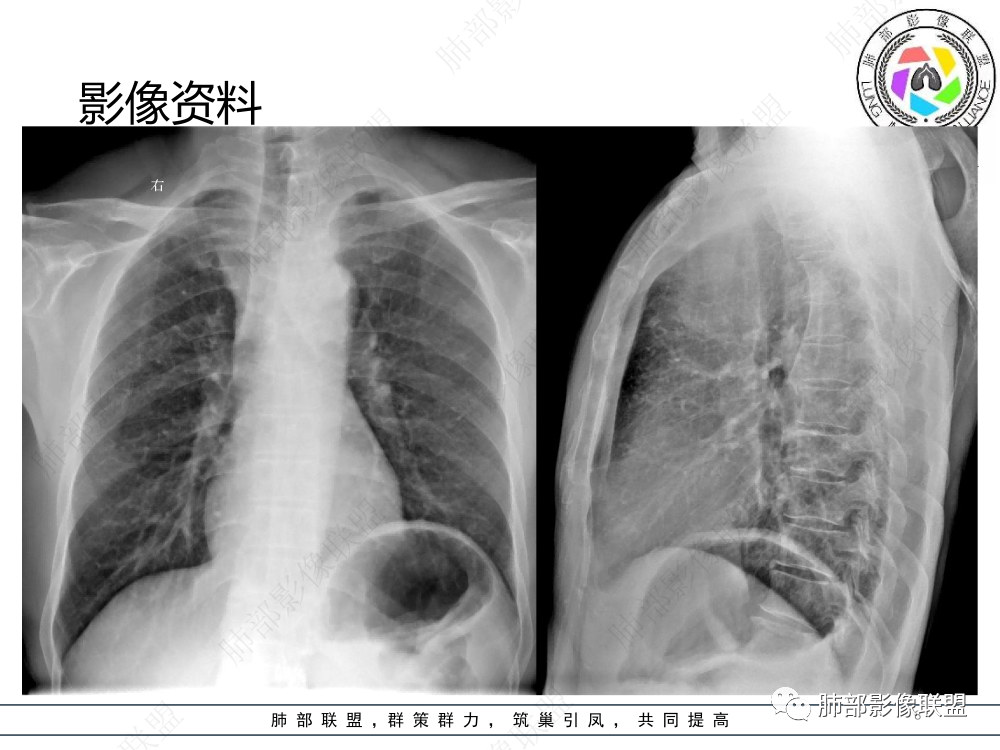

1.临床资料:中老年男性,病史较长-8个月,主诉胸痛,实验室资料:乳酸脱氢酶(LDH)升高。

2.影像表现:前上纵隔较大肿块,密度不均,形态不规则,边界不清,有结节样突起,脂肪间隙显示不清。病灶侵犯左无名静脉及上腔静脉,其中左无名静脉闭塞(胸背部侧支循环明显,亦表明回流受阻)。增强后轻中度不均强化。坏死边界欠清晰。可见心包积液,提示心包受侵犯。右侧上叶及纵隔胸膜下结节影,疑胸膜肺转移可能。胸骨柄后缘皮质不完整,疑骨质破坏(未提供骨窗及矢状位图像)。左锁骨上可见肿大淋巴结。